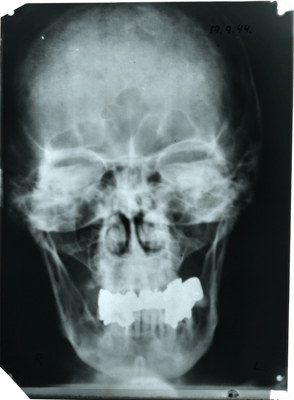

5. Since it’s at Stanford, unless the surgeon loses the corkscrew inside, I’m sure there’s a chance that my IQ will go up, all the way to 100. I attended a week of classes at Stanford in 2004, on the Great Depression and World War II, and got to hold this X-ray of Hitler’s skull, from the Hoover Institution, so all of this is very symmetrical.